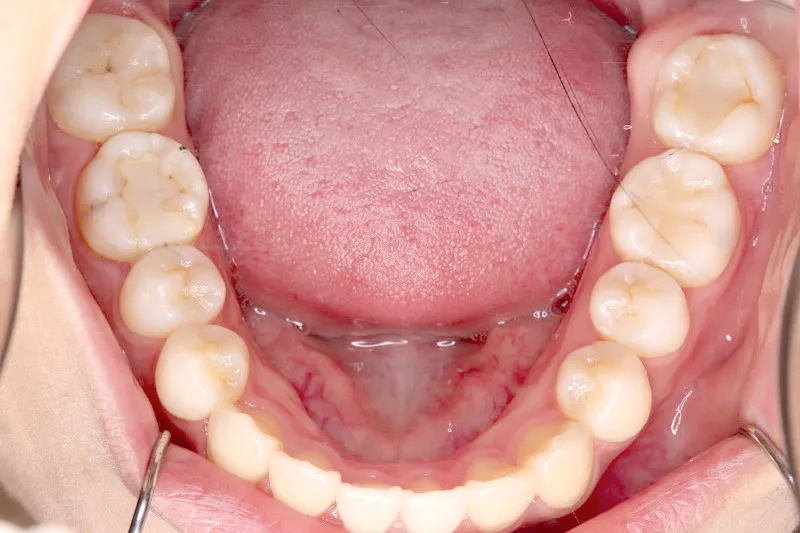

治療終了後

上下前から見える装置をつけ治療しました。歯は抜いてないです。

治療回数57回、6年9ヶ月の治療期間で矯正治療を終了しました。

主訴が改善され、ご満足頂きました。